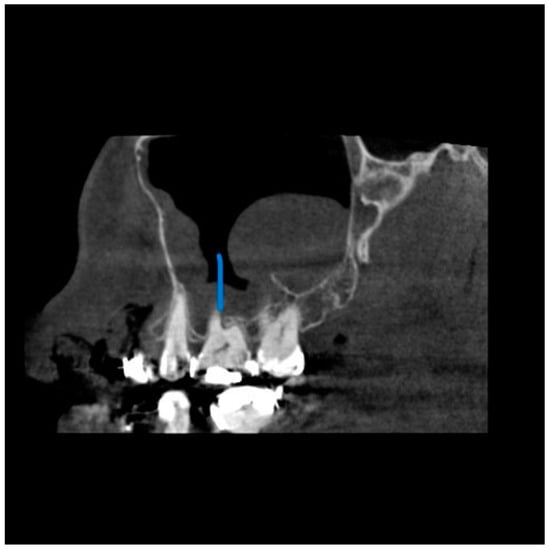

A total of 68 patients had pathologic findings in one or both sinuses, such as mucosal thickening, odontogenic cysts, fracture, hypoplasia, and bone lesions (58.1%) (Figure 1, Figure 2, Figure 3 and Figure 4). Of the 55 male patients, 33 had pathologies, like oroantral communication and inflammatory cysts in either sinus, whereas only 35 of the 62 scans of the female patients revealed radiographically abnormal findings in either sinus. The difference between the male and female patients was insignificant (Table 1).

Figure 3. View from the coronal plane. The Blue arrow shows a polypoid growth along the floor of the right maxillary sinuses.